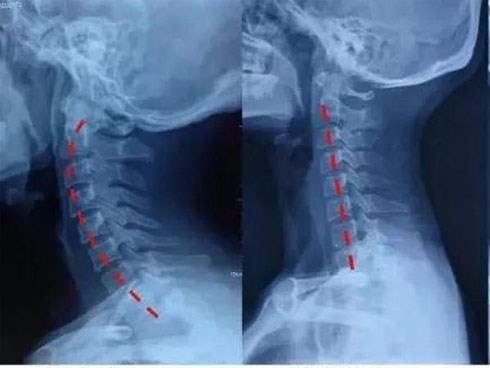

Nhìn phim chụp X-quang cổ của con, mẹ hối hận tột cùng khi trót để con sớm chơi thứ này

Thông tin có một cậu bé 9 tuổi bị chấn thương cột sống cổ do cúi đầu chơi điện thoại, đang là lời cảnh tỉnh cho tất cả mọi người, đặc biệt các bậc cha mẹ thường xuyên cho con sử dụng điện thoại di động.